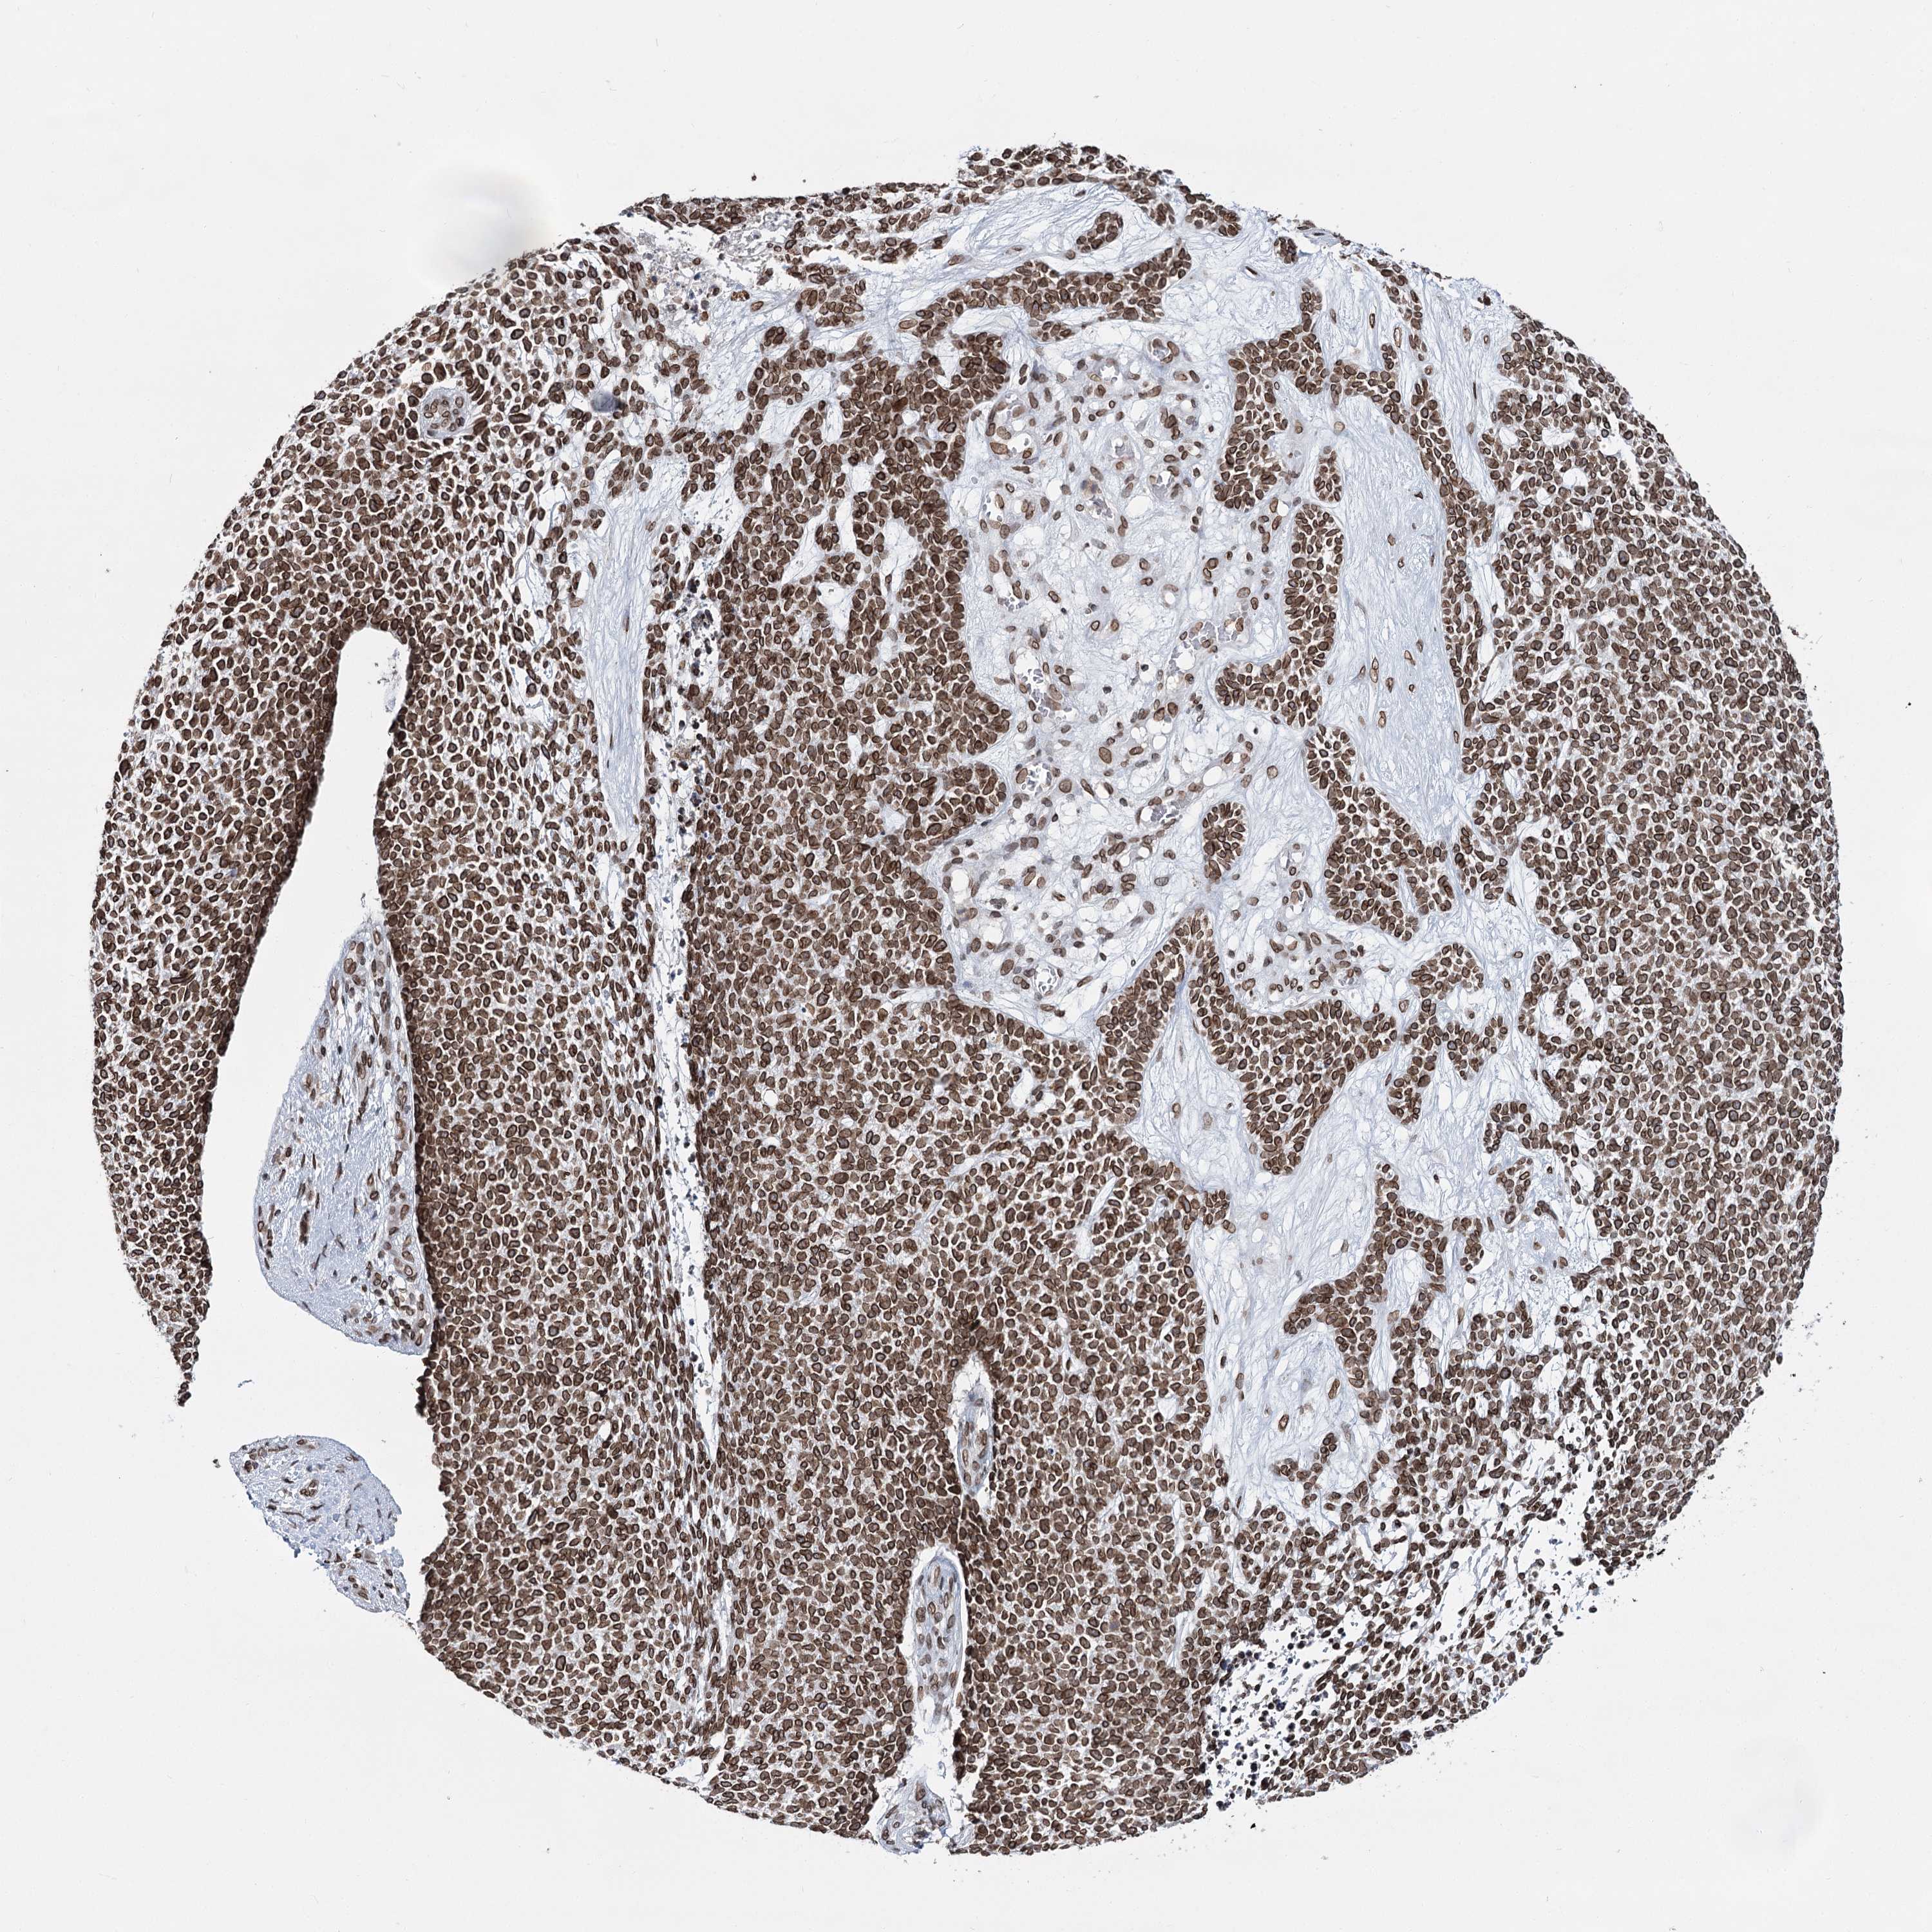

SKIN CANCER - Protein expressioni

A mouse-over function shows sample information and annotation data. Click on an image to view it in a full screen mode. Samples can be filtered based on level of antibody staining by selecting one or several of the following categories: high, medium, low and not detected. The assay and annotation is described here.

Antibody staining in the annotated cell types in the current human tissue is reported as not detected, low, medium, or high, based on conventional immunohistochemistry profiling in selected tissues. This score is based on the combination of the staining intensity and fraction of stained cells.

Each image is clickable and will lead to virtual microscopy that enables deeper exploration of all samples and also displays staining intensity scores, fraction scores and subcellular localization as well as patient and tissue information for each sample.

Antibody HPA038091

Staining

High

Intensity

Strong

Quantity

>75%

Location

Nuclear

Basal cell carcinoma